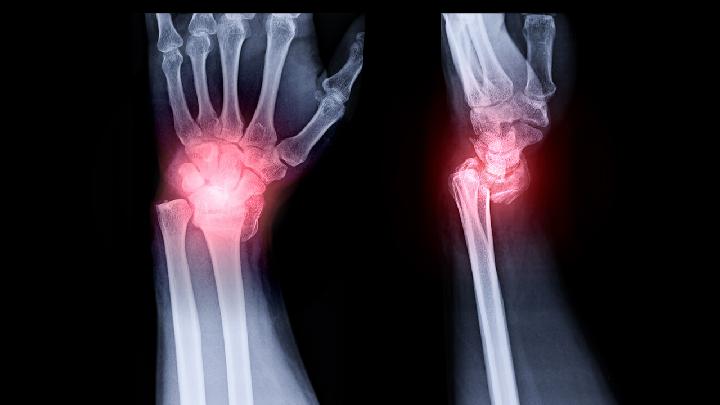

骨癌的诊断有的比较容易,单凭临床检查即可作出初步诊断,如表浅部,位的骨瘤或骨软骨瘤等,有的在x线片上有特点,可根据典型的x线所见得出初步印象如硬化性骨肉瘤、软骨肉瘤等;有的则须结合临床、x线和病理,综合分析,才能作出正确诊断。因此,临床、x线和病理被认为是诊断骨肿瘤的三个重要步骤,有时是缺一不可的。尤其在考虑采用截除肢体的手术之前,一般都要经过上述三方面的检查确诊,才能决定。